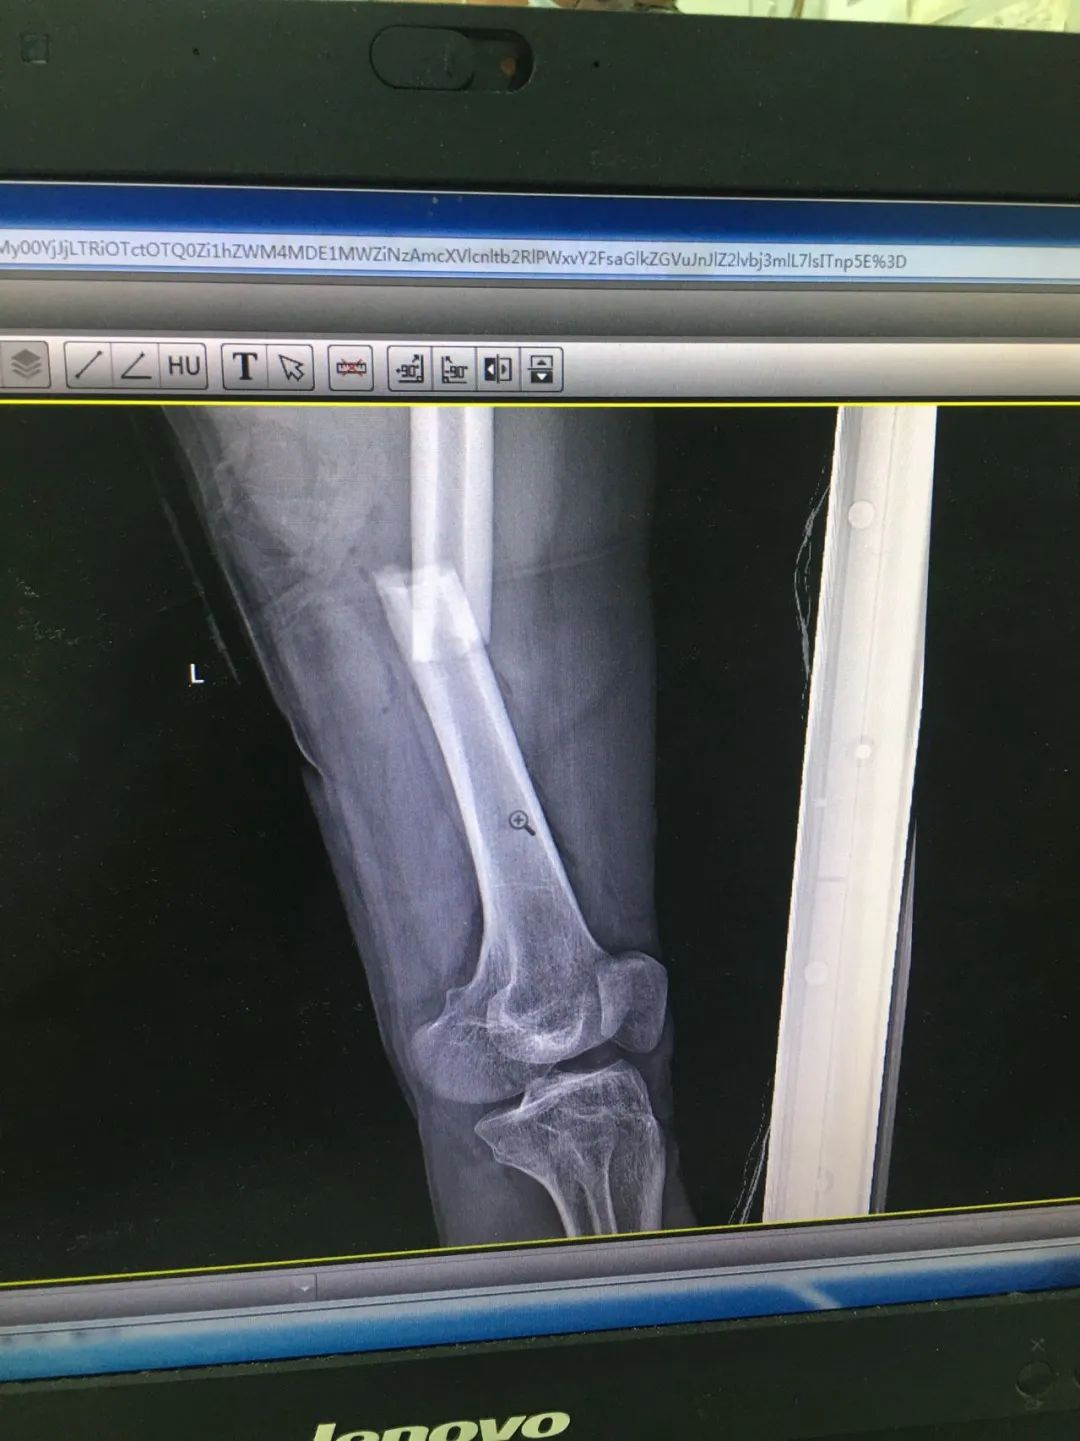

入院時,劉先生已失血性休克。急診科為劉先生安排X線及CT攝片檢查,顯示左股骨干、左腓骨上端骨折,左脛骨遠端粉碎性骨折,頭皮及全身多處皮膚軟組織挫裂傷,隨后收治于骨科。

第1次手術(shù)10天后,骨科為劉先生安排了第2次手術(shù),歷經(jīng)3個小時,成功完成左股骨干骨折及左脛骨遠端骨折閉合復(fù)位內(nèi)固定術(shù),植入兩根30cm×10mm、34cm×10mm髓內(nèi)釘。

術(shù)后一周,患者手術(shù)切口愈合良好,左下肢皮膚感覺及肌力正常,左足末梢循環(huán)恢復(fù),復(fù)查X片顯示骨折復(fù)位標(biāo)準(zhǔn),內(nèi)固定物位置良好。